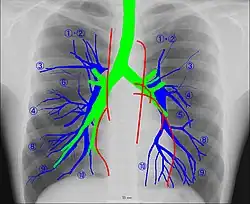

Anatomie radiographique d'une poitrine humaine.

La radioanatomie est une technique utilisée dans le domaine de l'anatomie qui repose sur l'exploitation de films radiographiques[1]. Le film radiographique représente l'image bidimensionnelle d'un objet tridimensionnel en raison de la projection de différentes structures anatomiques sur une surface plane.

En raison des compétences nécessaires à la lecture correcte des images, l'anatomie radiologique est la base de la formation des radiologistes, et une composante de la formation des étudiants en médecine.